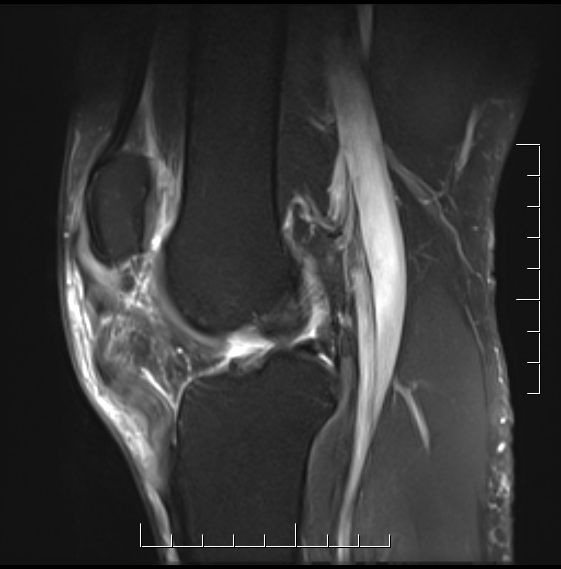

MRI

In chronic cases may only detect that tendon not attaching to distal pole patella